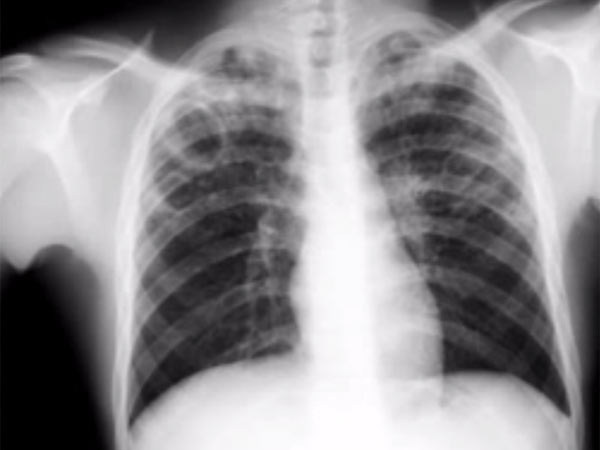

இந்தியாவில் 10 லட்சம் பேருக்கு டிபி!

டெல்லி: இந்தியாவில், 10 லட்சம் பேருக்கு, மிக மோசமான காச நோய் பாதிப்பு ஏற்பட்டுள்ளதாக, உலக சுகாதார நிறுவனம் எச்சரித்துள்ளது.

கடந்தாண்டு மட்டும், இந்தியாவில், 2.7 லட்சம் பேர், இந்த நோய்க்கு பலியாகியுள்ளதாகவும், சுகாதார நிறுவனம் கூறியுள்ளது.

கடந்தாண்டில் மட்டும், 4.5 லட்சம் பேர், புதிதாக இந்த நோயால் பாதிக்கப்பட்டுள்ளனர். இவர்களில் பெரும்பாலானோர், இந்தியா, சீனா, ரஷ்யாவைச் சேர்ந்தவர்கள்.

ஒருவரிடமிருந்து, மற்றவருக்கு, காற்று மூலமாக பரவுவது, காச நோய். இந்த நோயால் பாதிக்கப்பட்டவர்களுக்கு, கடுமையான, தொடர்ச்சியான இருமல், சளி, காய்ச்சல், பசியின்மை, உடல் எடை குறைதல் போன்றவை இருக்கும்.

காசநோய் மரணங்கள்

இந்தியாவில் மட்டும், காசநோயால் மிக மோசமாக பாதிக்கப்பட்டு, கடந்தாண்டில், 2.7 லட்சம் பேர் இறந்து உள்ளனர். காசநோயால் பாதிக்கப்பட்டவர்களில் பெரும்பாலானோர், அதற்கான சிகிச்சையை பெறாமலேயே, இருக்கின்றனர் என்றும், சுகாதார நிறுவனத்தின் ஆய்வு, அடுத்த அதிர்ச்சி குண்டை போட்டுள்ளது.

உலக அளவில்

உலக அளவில்3ல்ஒருவருக்கு காசநோய் பாதிப்பு இருப்பதாக கண்டறியப்பட்டுள்ளது. இந்தியா, தென்ஆப்பிரிக்க நாடுகளில்தான் டிபியினால் அதிக மரணங்கள் நிகழுகின்றன.

இந்தியா, சீனா, தென் ஆப்பிரிக்கா, இந்தோனேசியா மற்றும் பாகிஸ்தான் நாடுகளில்தான் அதிக அளவில் டிபி யினால் பாதிக்கப்பட்டுள்ளனர்.

பெண்கள்-குழந்தைகள்

8.6 மில்லியன் பேர் காசநோயினால் பாதிக்கப்பட்டுள்ள நிலையில் 0.5 மில்லியன் குழந்தைகளும், 2.9 மில்லியன் பெண்களும் இந்த நோயினால் பீடிக்கப்பட்டுள்ளனர்.